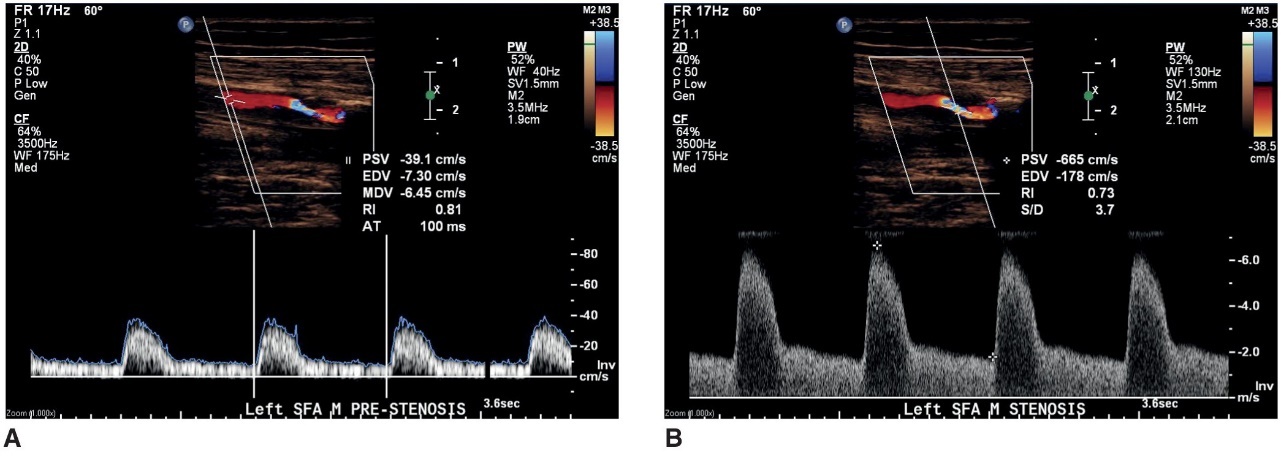

when disease is present (stenosis)

velocities and waveforms should be recorded proximal to the stenosis, in the stenosis, and distal to the stenosis

a doppler waveform taken proximal to a stenosis

what does image A represent

a doppler waveform taken at the area of maximum velocity shift within a stenosis

what does image B represent